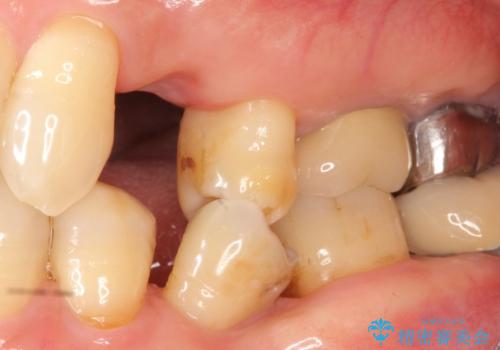

歯がわれた 抜歯してインプラント 50代男性

- 歯ぐきの腫れと痛みを主訴に来院された患者様です。

精査したところ、歯が割れており保存不可能な状態であったためやむなく抜歯しました。

患者様のご希望によりインプラント治療を行いました。